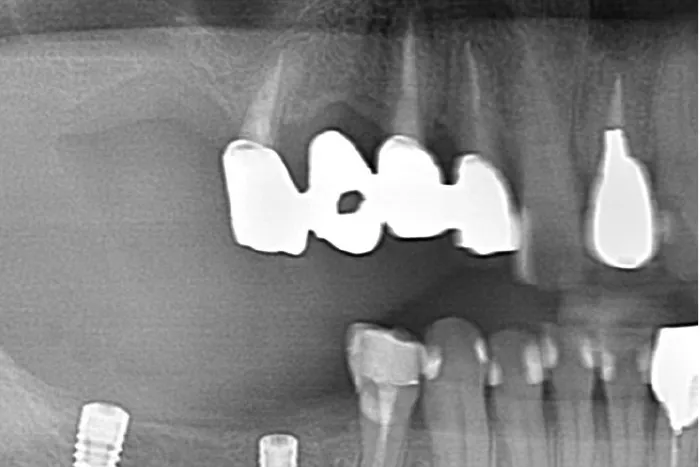

S R Pでは、縁下歯石を盲目的に除去します。

特に6mm以上の深いポケットでは熟練した衛生士であっても全ての歯石を取り除くことは不可能です。

なので、外科的にフラップを開けることによって明視野で取りきれなかった歯石を全て取ります。

歯周外科を行うことによって、歯根面は空気に触れるので嫌気性菌は減少します。

しかし、深いポケットを改善しないままだと、また嫌気性菌が繁殖してしまいます。

環境改善のため歯周ポケットの除去同時にを行います。